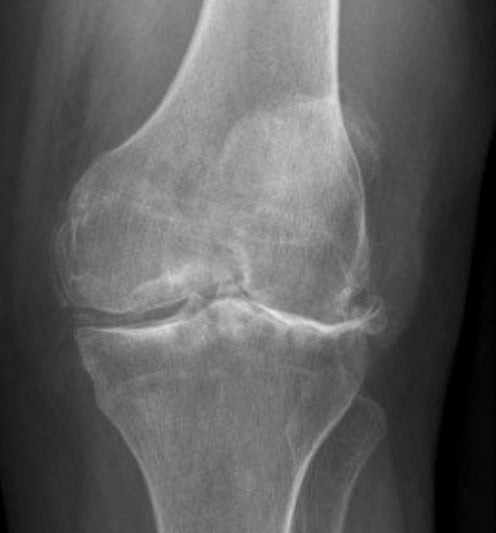

- X-ray images can reveal joint space narrowing, bone spurs, and other changes associated with arthritis as well as providing important information about your bony alignment.